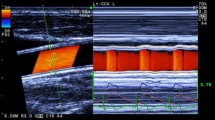

During exercise, HR increases with an increase in workload; therefore, atrial pacing is not needed for changing HR. It has also been demonstrated that the peak dP/dt−HR relation is markedly enhanced (the slope is increased) during exercise compared with during pacing in normal hearts, but the enhancement is limited in diseased hearts [8]. The FFR obtained by exercise may have higher power to discriminate cardiac contractile states than that obtained by pacing. In spite of its potential for evaluating cardiac function during exercise, peak dP/dt−HR relation has not been widely used because of its invasive nature. We have reported that carotid arterial wave intensity (WI) noninvasively measured with a combined system of color Doppler and echo tracking is a sensitive index of global LV contractile function (Fig. 1) [9, 10].

Figure 2 shows the WD waveform calculated from the diameter-change waveform and the velocity waveform.

According to Eq. 4, the maximum value of carotid arterial WD during a cardiac cycle (WD1) correlates with the maximum value of WI (W1). Therefore, WD1 correlates with peak dP/dt as W1 does (Fig. 1). WD is obtained by measuring U and D without measuring upper arm pressure (Fig. 3), which is easier to perform during exercise. The details of the method of measurements were described elsewhere [11].

Measurements of diameter-change waveform and blood velocity. Left Long axis view of the common carotid artery and ultrasound beams. By setting the tracking positions displayed as small pink bars on the echo tracking beam (line A) to arterial walls, echo tracking automatically starts. The blood flow velocity averaged along the Doppler beam (line B) crossing the artery was measured using range-gated color Doppler signals. Right The diameter-change waveform, which is calculated by subtracting the distance to the near wall from that to the far wall, is displayed on the M-mode view. The blood flow velocity waveform is also displayed on the M-mode view

Subjects were asked to refrain from caffeine, alcohol, and exercise during the 24-h period before the test. Before the measurements of WD1 and HR, the subjects were laid down the supine position for 10 min. The location to be measured was the right common carotid artery at about 2 cm proximal to the carotid bulb. We used scanning in the long axis view, and obtained a B-mode image of a longitudinal section of the artery (Fig. 3, left). With the B- and M-mode scans displayed simultaneously on a split screen, the echo tracking system tracked the vessel wall movements to produce displacement waveforms of the anterior and posterior artery walls (Fig. 3, right). This gave the diameter-change waveforms.